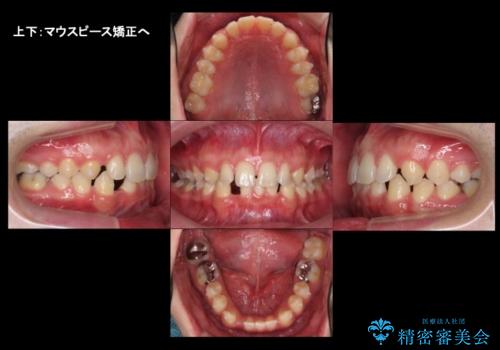

すきっ歯・出っ歯 コンプレックスの前歯を治したい 目立たない方法で セラミック治療は不可能な症例

- 前歯の並びを治したいと来院。

人前に立つ予定があるとのことで、初めはセラミックで歯を削ってかぶせる短期間で終える治療を希望されていました。

歯の位置が悪く、隙間も大きいためセラミックで被せても到底思ったような仕上がりにならないこと、下の歯が咬み込んでいるためセラミックはおろか前歯が短期間で折れてしまうリスクが非常に高いことを説明しました。

上はインビザラインで目立たないように前歯を下げ、下は難しいため、ワイヤー矯正で咬み込んでいる下の歯を沈める処置を初め行いました。最終的には上下ともインビザライン矯正で仕上げました。

下の前歯が生まれつき1本少なかったため、その部分には最終的にインプラントを入れ、下の歯が下がりすぎないようにかつ上の前歯にしっかり咬むように仕上げました。